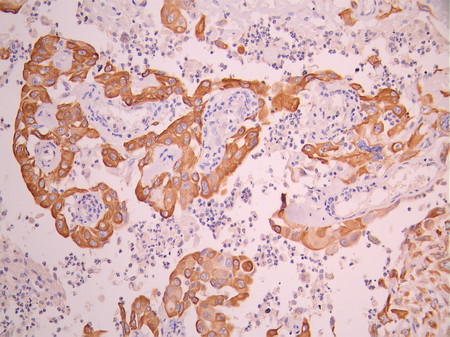

IHC image of CSB-RA957044A0HU diluted at 1:100 and staining in paraffin-embedded human tonsil tissue performed on a Leica BondTM system. After dewaxing and hydration, antigen retrieval was mediated by high pressure in a citrate buffer (pH 6.0). Section was blocked with 10% normal goat serum 30min at RT. Then primary antibody (1% BSA) was incubated at 4°C overnight. The primary is detected by a Goat anti-rabbit polymer IgG labeled by HRP and visualized using 0.05% DAB.

IHC image of CSB-RA957044A0HU diluted at 1:100 and staining in paraffin-embedded human cervical cancer performed on a Leica BondTM system. After dewaxing and hydration, antigen retrieval was mediated by high pressure in a citrate buffer (pH 6.0). Section was blocked with 10% normal goat serum 30min at RT. Then primary antibody (1% BSA) was incubated at 4°C overnight. The primary is detected by a Goat anti-rabbit polymer IgG labeled by HRP and visualized using 0.05% DAB.